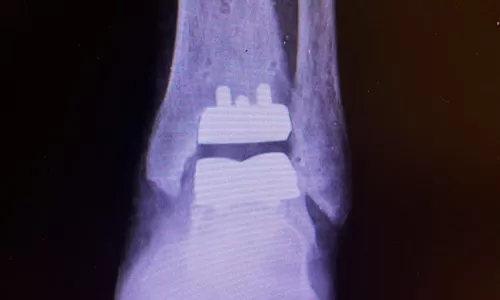

Hoje em dia, em grande parte dos casos, realizamos a artroplastia do tornozelo, quando se faz a substituição da articulação doente (tornozelo com artrose) por uma articulação metálica (prótese de tornozelo). Neste tipo de tratamento obtemos a melhora da dor com a manutenção do movimento articular.